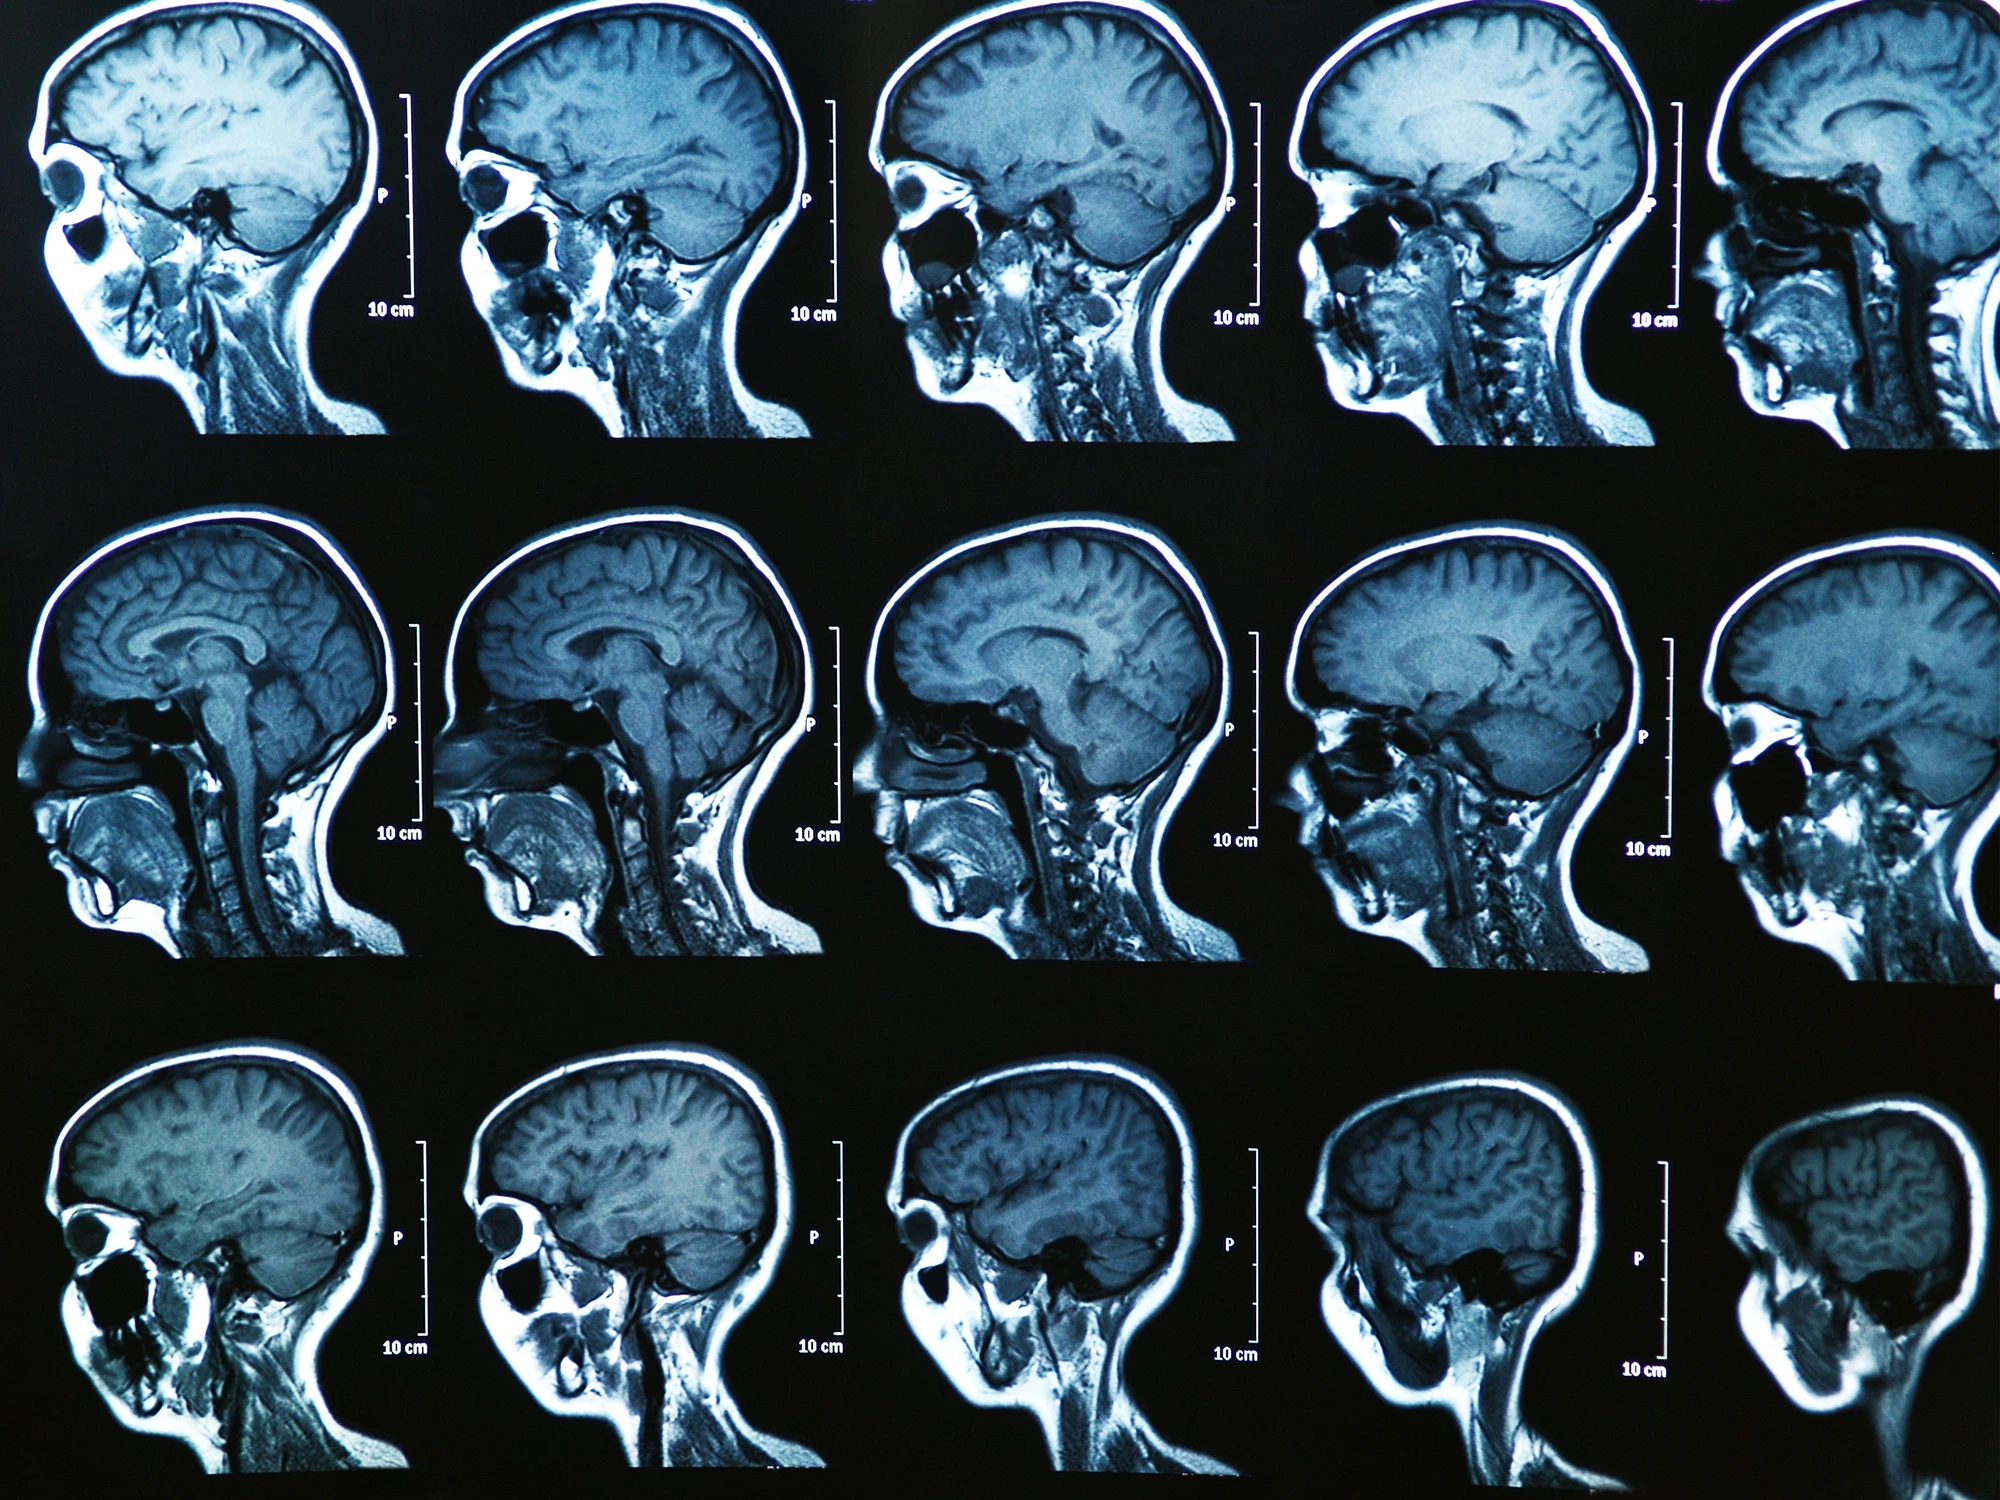

MRI brain scans of MS patients, based on the newly identified subtypes

The team set an AI tool called Subtype and Stage Inference (SuStaIn) to work on the MRI brain scans of 6,322 MS patients. In doing so, it identified three new subtypes of MS, which the scientists later named “cortex-led,” “normal-appearing white matter-led,” and “lesion-led.” These names are based on where and what type of abnormalities appear earliest.